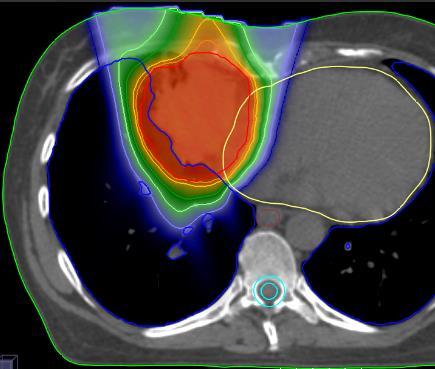

11:30 Proton therapy for lung cancer Judith van Loon, MAASTRO clinic, Maastricht, NL

Fra 2024 kan pasienter tilbys protonterapi i Norge. Vi ønsker å samle fagfolk med interesse for stråleterapi innen GI-, bryst- og lungekreft for å diskutere hvilke nye muligheter protonterapi gir oss og hvilke protokoller/studier som bør initieres. Påmelding innen 7. feb. 2020 på https:// forms.gle/h6d213FWVsLjXb269. Antall plasser er begrenset. Dersom overbooking vil det gjøres en prioritering slik at alle fagområder blir representert. Bekreftelse av plass blir utsendt innen 12. feb. Parallelle diskusjoner - Brystkreft - Lungekreft - Gastrointestinal kreft